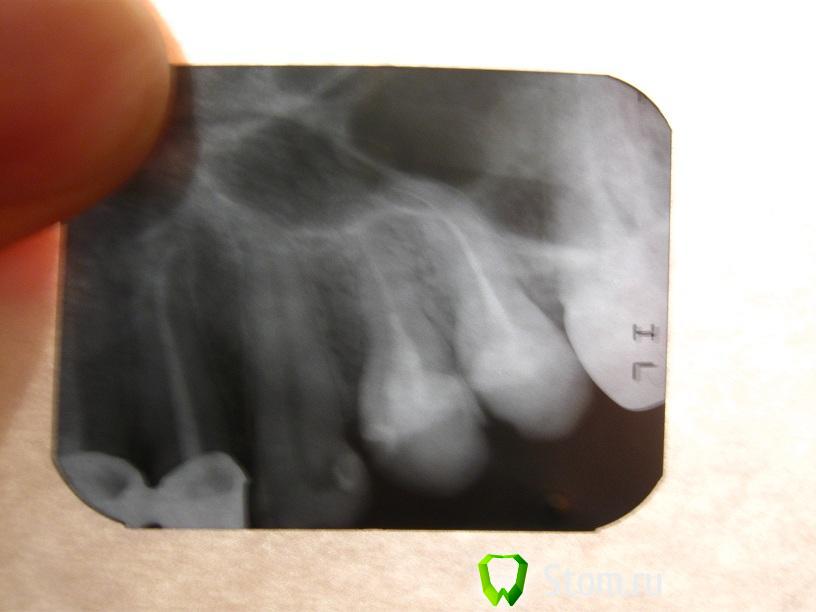

Krio Опубликовано 8 февраля, 2012 Автор Поделиться Опубликовано 8 февраля, 2012 здравствуйте еще раз!с некоторым запозданием выкладываю снимок.интересует 3-й зуб возле коронокспасибо! Ссылка на комментарий

Scrabble Опубликовано 8 февраля, 2012 Поделиться Опубликовано 8 февраля, 2012 А Вы говорили, пломб нет. Посмотрите внимательно на фото и снимок. Если зуб не беспокоил никогда, можно старую пломбу поменять и сделать винир. Ссылка на комментарий

Krio Опубликовано 8 февраля, 2012 Автор Поделиться Опубликовано 8 февраля, 2012 Scrabble, да, на снимке действительно похоже на пломбу) наверное, в школе еще ставили, вот и не помню.а почему Вы рекомендуете виниры? реставрация хуже держится, непрочна? и еще просьба глянуть вот этот снимок 6-го нижнего. есть ли сейчас какое-то воспаление или аномальные процессы в кости или тканях? в последнее время какие-то ощущения в нижней челюсти с этой стороны. депульпировали год назад. спасибо! Ссылка на комментарий

Scrabble Опубликовано 8 февраля, 2012 Поделиться Опубликовано 8 февраля, 2012 (изменено) "Реставрация"-это по сути пластмасса, по эстетике и сроку службы её с керамикой не сравнить. 47 сделан всё-таки похуже 46, проблема пока в нём, мне кажется. Изменено 8 февраля, 2012 пользователем Scrabble Ссылка на комментарий